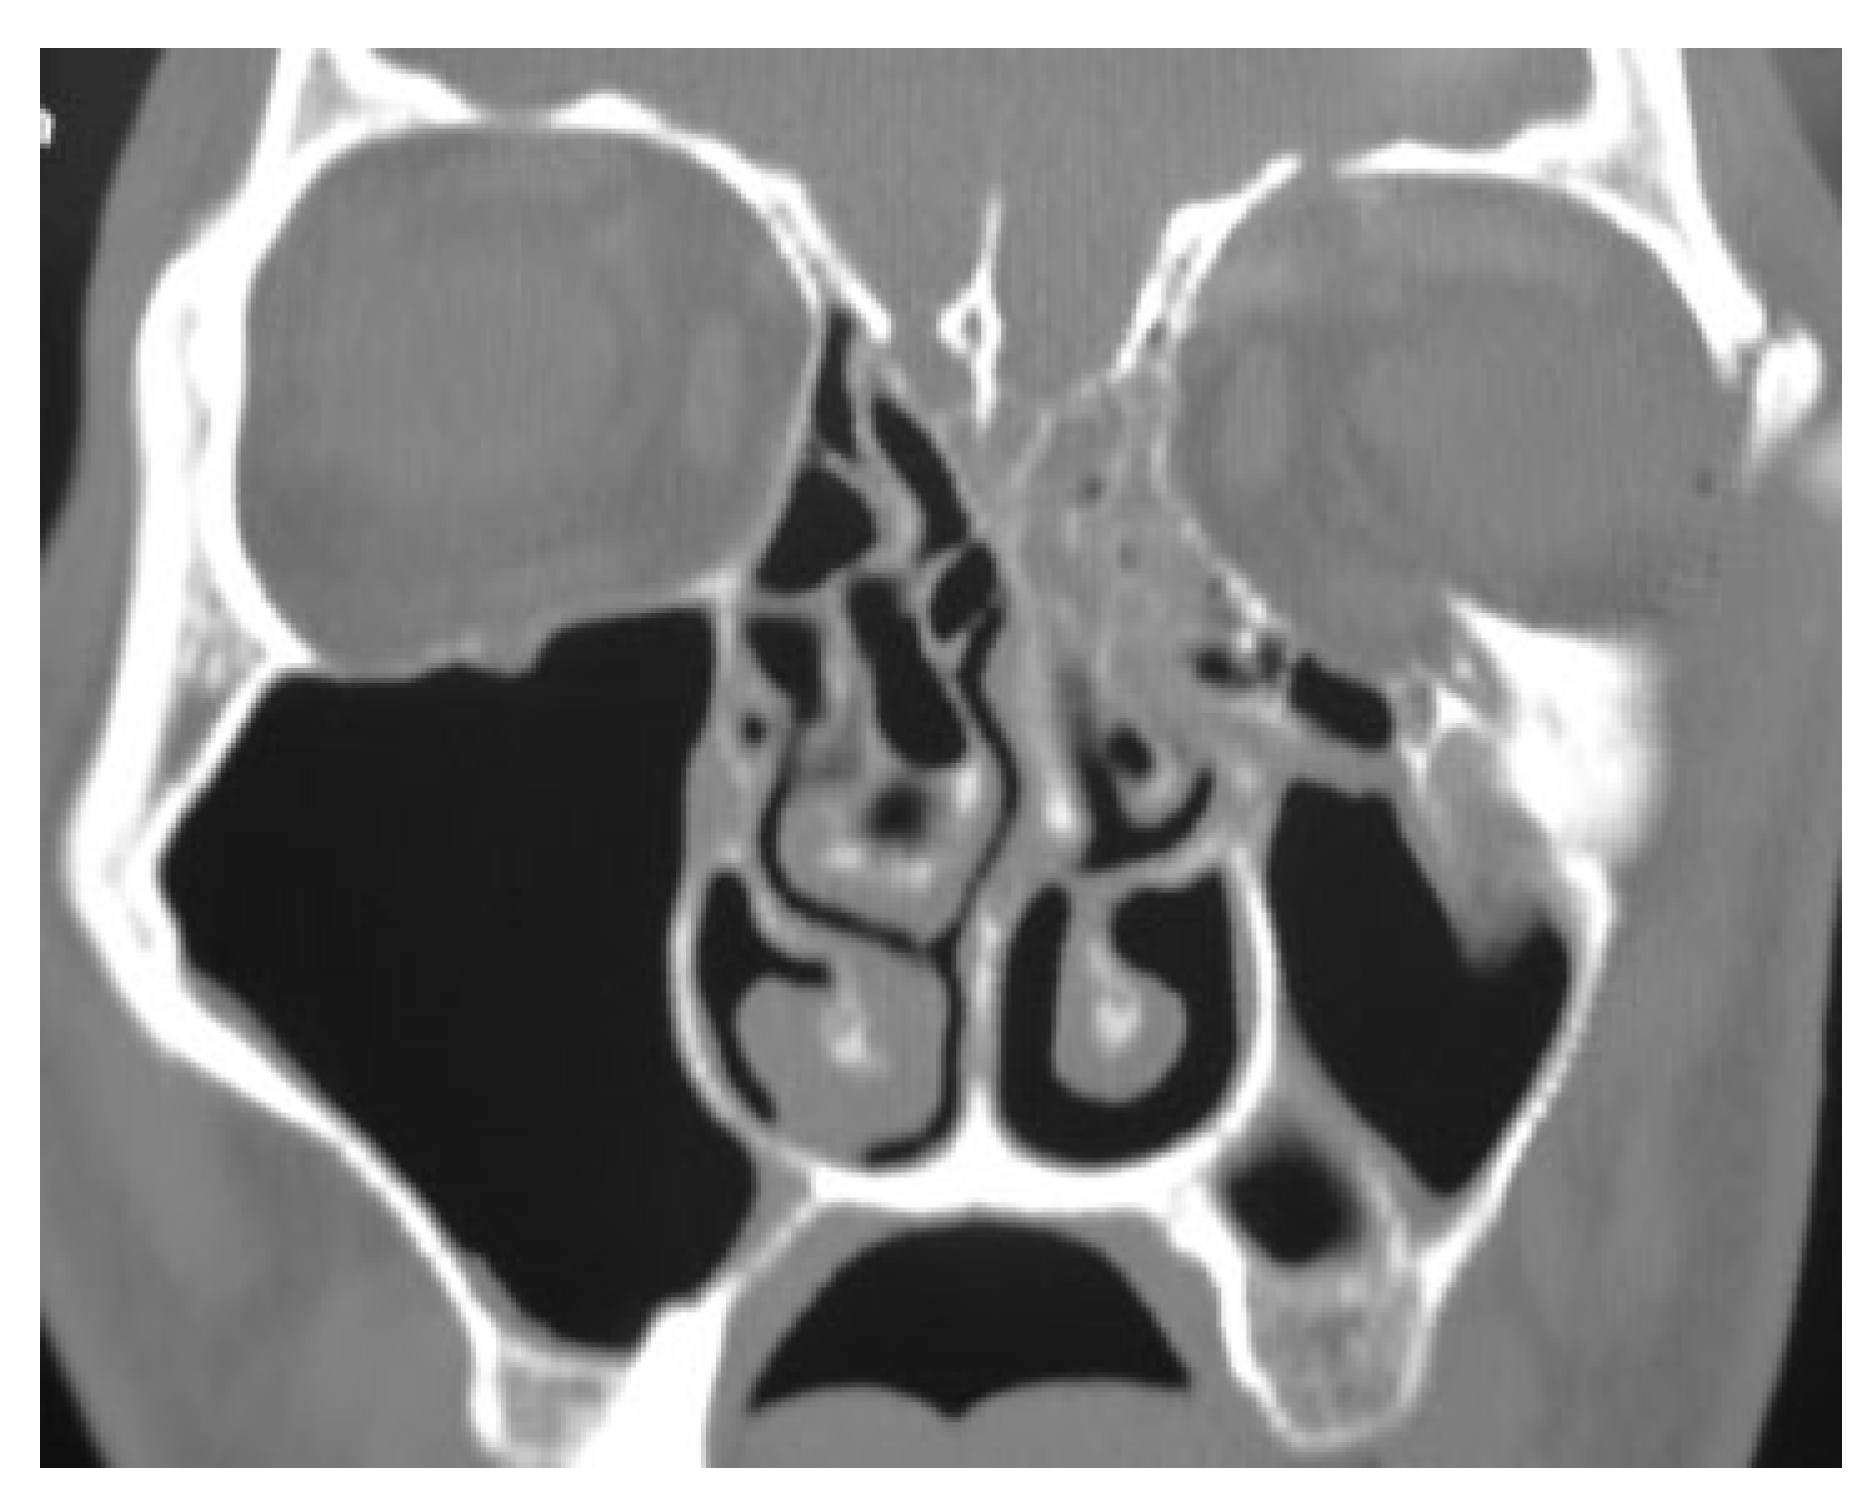

In this prospective study different parameters using biode-gradable plates for reconstruction of the blow-out fractures were assessed. The study was approved by the research committee of the medical ethics group of Shiraz University of Medical Sciences. The study sample was derived from the patients who referred to the Department of Craniomaxillo-facial Surgery for evaluation and management of orbital fracture between January 2009 and December 2010. Patients eligible for study inclusion had an impure blow-out fracture and there was a need to repair orbital floor and to fix the zygomaticomaxillary complex in a proper position. Patients who had pure blow-out fracture or minimal bone displace-ment in computed tomography (CT) scan views without the enophthalmos or the diplopia were excluded from the study. All the patients had a recent trauma and subsequently surgi-cal intervention was made between 1 and 10 days. A consul-tation was made with ophthalmologist before the surgical intervention. An axial and coronal CT scans were taken through 2-mm cuts for each patient before surgical interven-tion, immediate, and 18 months after surgery (Figure 1 and Figure 2). The amount of the orbital floor defect was measured in each case through CT scan. The surgical approach consisted of mid-lower incision for accessing the orbital rim and floor. Bone reduction and reconstruction was made through biode-gradable plate (PG910/PDO) (Figure 3). Titanium miniplates and screws were used for fixation of fractured infraorbital rim. The thickness of the biodegradable plates (PG910/PDO) was 0.5 mm. All the patients underwent secondary interven-tion to remove the titanium miniplates after 18 months. The orbital floor was reevaluated during the secondary interven-tion. The evaluation of remnant defects and biodegradable plates (complete or partial resorption) was made for every patient (Figure 4).

Figure 3. Image demonstrates placing a biodegradable plate on the orbital floor.